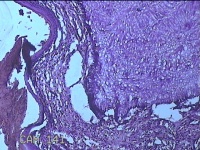

宫颈赘生物

性别

女

年龄

37岁

临床诊断

早期人工流产;宫颈炎性疾病

一般病史

宫颈有1赘生物。

标本名称

大体所见

灰白暗红色肿物1.3x0.8x0.2cm一个,表面糜烂。